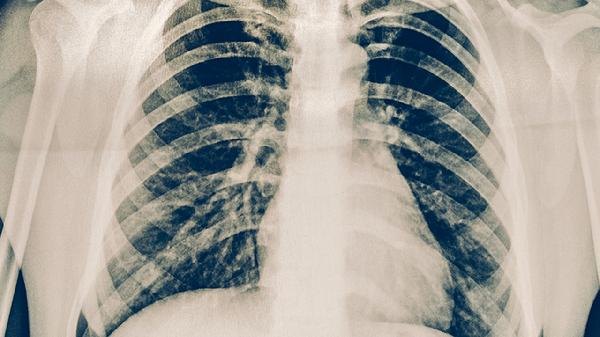

皮肤结核表现为红斑、结节、溃疡等皮损,常见类型包括寻常狼疮、疣状皮肤结核等。肺结核典型症状为咳嗽、咯血、低热、盗汗等呼吸系统症状,胸部影像学可见肺实质病变。

皮肤结核需通过皮损组织病理检查发现结核结节,配合抗酸染色或PCR检测确诊。肺结核诊断依赖痰涂片找抗酸杆菌、痰培养、胸部CT等检查,必要时需进行支气管镜检查。